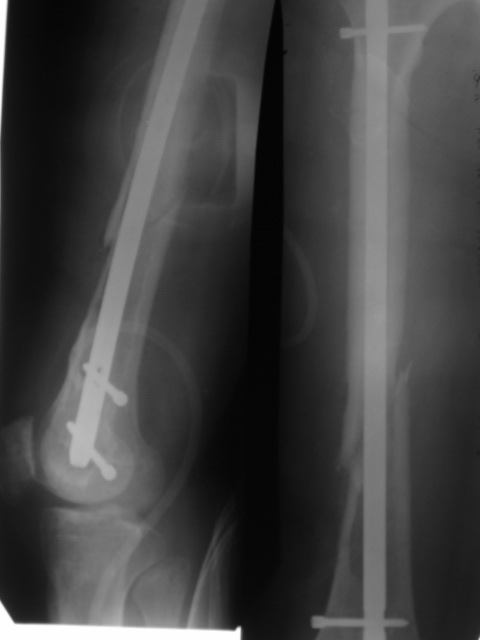

Приветствую, коллеги. 2 года назад пациентке поставлен диагноз саркома бедра,

Реостеосинтез |  Сегодня |  |  |  | 1.5 года назад произведен синтез для улучшения качества жизни для по поводу патологического перелома на уровне открытой биопсии. Через 4 месяца открытый реостеосинтез с исправлением оси и восстановления опроспособности. В период после перелома лучевой и химиотерапии не получала. Месяц назад появилсь возрастающие боли в суставе. Ходит с тростью. Движения в коленном суставе качательные.На рентгеннограммах после реостеосинтеза намечалась тенденция к сращению. В области операционной раны периодически открывался-закрывался свищ. На последних - кроме миграции гвоздя в сустав - лизис костной мозоли. Можно ли одной из причин миграции считать длительную статическую фиксацию гвоздя? У кого-нибудь есть опыт на каких сроках проводить у онкобольных динамизацию? Что можно сделать для ликвидации боли и поддержания опороспособности конечности? Имеет ли смысл установка более толстого фиксатора без дистального блокирования? И вообще,ставить ли здесь вопрос о сохранении конечности?

Саркомные переломы обычно не срастаются, по этому не зависимо от места метастаза фиксатор устанавливается максимально длинный и обязательно с блокировкой что бы сохранять длину кости даже после роста метастаза или при дополнительно метастазировании. В Вашем случае блокировочные гвозди выглядят тонкими и проведены только через один кортекс. Гвоздь толщиной более 10 мм с блокировочными шурупами 4-5 мм проведенные через обе кортикальные пластинки может обеспечить опороспособность даже если перелом не срастется или литический процесс распространится.